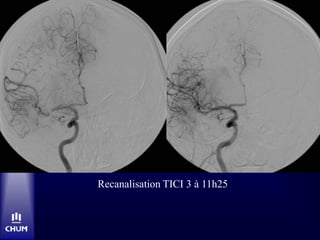

Recanalisation TICI 3 à 11h25

Bolus tPA-IV à10h15 CTA-Source Images

CT C- à48 heures Congé jour 5 avec NIHSS 1